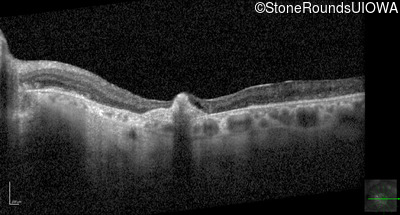

Optical Coherence Tomography - Left - 20/100

Exemplar / OCT Stack